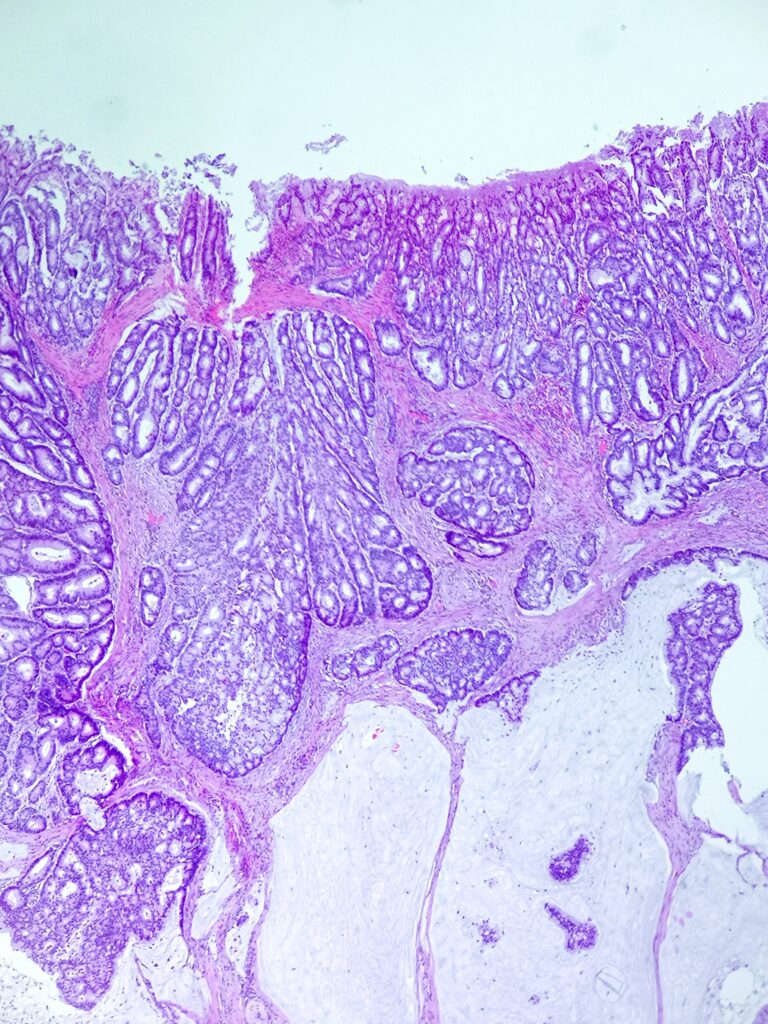

Pacjentka 61 letnia z guzem kątnicy wykrytym w trakcie diagnostyki obecności krwi utajonej w kale. Wykonano prawostronną hemikolektomię.

Do badania makroskopowego nadesłano fragment przewodu pokarmowego długości 55cm zawierający dystalny fragment jelita cienkiego długości 5cm oraz kątnicę, wstępnicę i fragment poprzecznicy. Do jelita przylega fragment sieci wymiarów 30x15x0,5cm. Na przekrojach w kątnicy, w odległości 2cm od zastawki krętniczo- kątniczej oraz około 45 od dystalnej linii odcięcia obecny jest płasko- wyniosły guz wymiarów 5×4,5×1,5cm, który w ocenia makroskopowej jest ograniczony do mięśniówki właściwej, nie nacieka przylegającej tkanki tłuszczowej ani surowicówki.

Obrazy mikroskopowe: